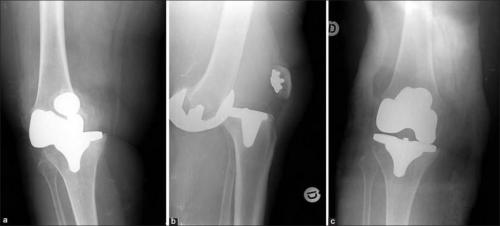

Такое может случиться, если очень торопиться. Это вывих коленного импланта.

Во время операции пораженные компоненты сустава заменяются на эндопротез (искусственный сустав), повторяющий форму здоровых, изготовленный из материалов, максимально схожих с натуральными тканями человека. Компоненты эндопротеза фиксируются при помощи костного цемента.

Современная конструкция эндопротеза коленного сустава состоит из бедренного и большеберцового компонентов. Технология его применения предполагает использование в качестве стабилизаторов естественные неповрежденные связки этого сустава. Таким образом, сохраняются естественные движения в суставе, и снижается риск разрушения эндопротеза. Хирург также вставляет пластиковые вкладыши, которые выполняют функцию хряща и снижают трение.

С учетом состояния костной ткани и анатомических особенностей колена эндопротез подбирается в индивидуальном порядке. Если поражена лишь одна область коленного сустава, то возможно проведение однополюсного, или частичного, эндопротезирования. При частичном эндопротезировании искусственный сустав замещает лишь поврежденный отдел коленного сустава.